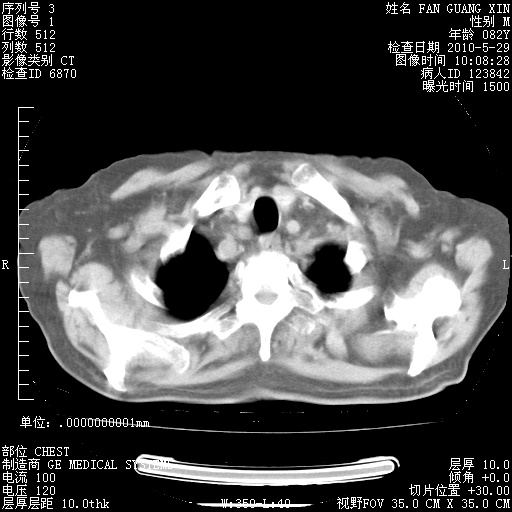

治疗3周后的肺部CT纵隔窗

再治疗10天后的肺部CT

再治疗10天后的肺部CT 纵膈窗

肺部体征:呼吸25次/分,心率100次/分,呼吸音增粗。无干湿罗音。

血常规:15.36×10 [sup]9[/sup]/L  N0.92  L0.036  M0.045 ESR 27mm/h。

血生化:白蛋白33.30g/L  球蛋白23.67g/L  CRP 32.82mg/L 肝肾功能正常。电解质正常。

从白细胞总数和中性比例看好像合并感染。肺部纹理好像比上次多,支气管炎?其他感染?

阅读此次胸部CT,肺间质渗出性改变较入院时有吸收。目前从体温、白细胞、中性分叶明显增高,肯定存在细菌感染(发生医院感染哦,若无消化道及泌尿系统等感染的依据,肺部感染可能大)。若你院头孢哌酮舒巴坦钠耐药率较高,同意你的方案,若48小时体温仍高,可考虑使用碳青霉稀类抗菌药物,同时可予超声雾化、注意滴数时加大液体量。白蛋白33.30g/L较低哦,需加强营养等支持治疗。